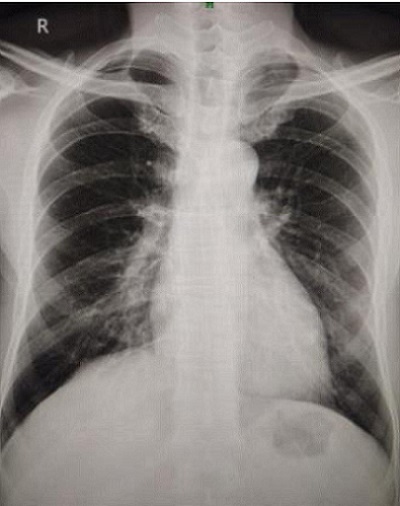

Case Presentation: A 60-year-old male with a history of chronic kidney disease presented with progressive weight loss over several months. He had previously been treated empirically for pulmonary tuberculosis for four months by a private practitioner without clinical improvement. On examination, the patient was afebrile with stable vital signs and normal oxygen saturation.

Computed tomography (CT) of the chest revealed a solid non-calcified nodule in the posterobasal segment of the left lower lobe along with patchy subpleural consolidation in the leftt upper lobe, raising suspicion of malignancy or granulomatous infection.